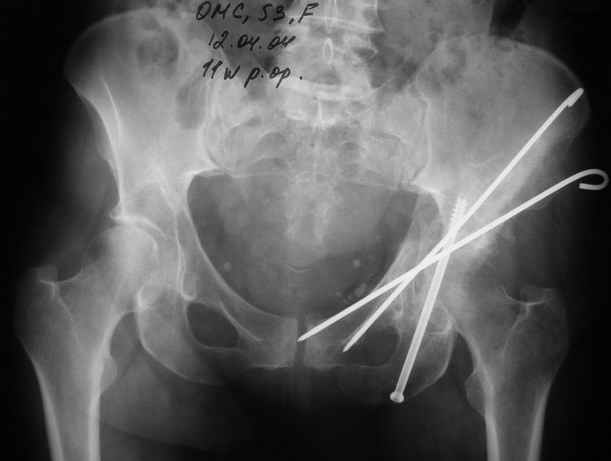

Anatoly F Lazarev 03 Сентябрь 2004, 22:18

Женя! Класный перелом. Отлично репонируется изнутри таза, но лучше фиксированть сзади. Классический перелом для двустороннего доступа.

Однако есть альтернатива. Репозиция из подвздошного доступа тазовыми щипцами с разнодлинными браншами или тазовым пистолетом, а фиксация задней колонны через седалищный бугор или тазрвыми винтами 4,5 или каннюлированными 6,5 или 7,3. По-моему я посылал на ортофорум такой снимок, когда жаловался на ишемический неврит седалищного нерва через сутки после операции. Не забудь про шейку бедра - мне кажется будет хорош длинный PFN любой фирмы, какую ты найдешь, а нет так UFN + miss a nail, как это здорово делают мои земляки - Ебурбуки. Пока.

12.04.04

02.06.04

Высылаю пример еще одного случая, остеосинтез пластиной из подвздошного доступа.